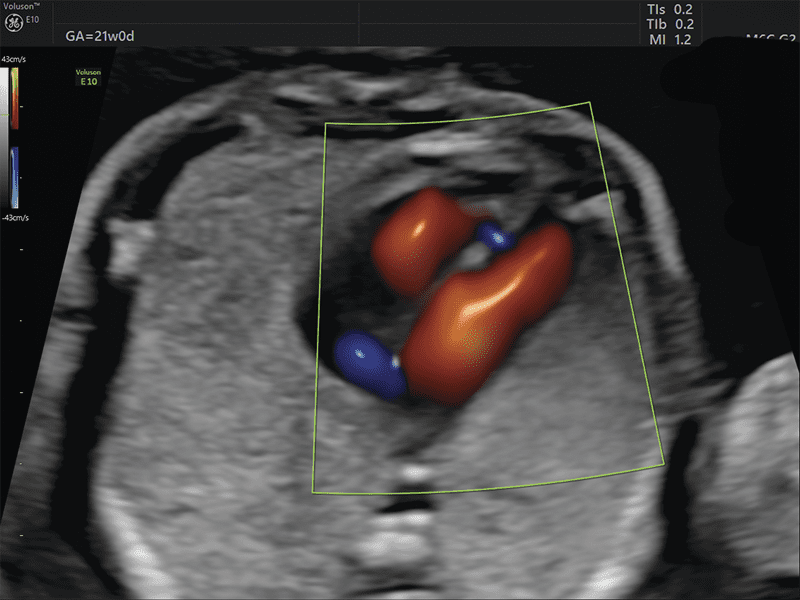

STIC: Per l’acquisizione 3D del cuore fetale, viene applicato un sofisticato algoritmo per la gestione e soppressione della distorsione causata dal movimento dei tessuti materni e fetali. Le immagini tomografiche sono riorganizzate in base alla fase del ciclo cardiaco e il data set 3D viene generato con solo immagini tomografiche nella stessa fase di ciclo cardiaco.

SonoVCAD Heart: strumento avanzato, basato sulla tecnologia Volume Ultrasound, CHE aiuta nella visualizzazione automatica delle scansione degli outflow cardiaci partendo dal volume data set acquisito. Permette una ricostruzione completa e automatizzata, relativa all’esame cardio fetale seguendo le linee guida delle società scientifiche AIUM, ACOG, ACR e ISUOG.

Semplicemente con due click il sistema è in grado di effettuare l’analisi e proporre le principali proiezioni.